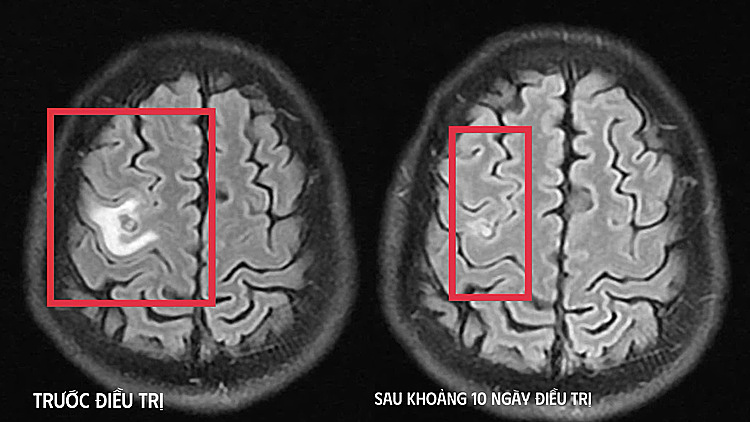

A cranial magnetic resonance imaging (MRI) scan revealed a small cystic lesion in the left frontal lobe with mild brain edema. This image strongly suggested a parasitic lesion rather than a primary brain tumor. Subsequent tests confirmed a positive result for dog tapeworm. Doctors diagnosed a parasitic brain lesion and initiated medical treatment, focusing on symptom control and close neurological monitoring. The patient's condition improved significantly after about 10 days.

Imaging before and after treatment. Photo: *Hospital provided*. |